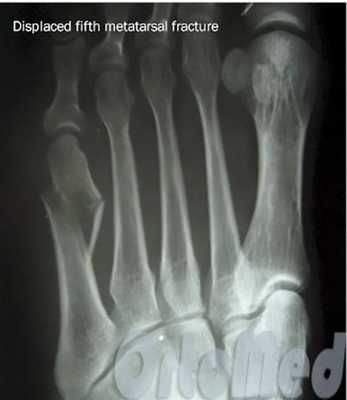

В ортопедической практике перелом плюсневой кости стопы достаточно распространен: на плюсневые кости приходится 35% переломов стопы. Около 80% из них протекают без смещения и считаются неосложненными. У взрослых и детей старше 5 лет преимущественно диагностируют повреждение пятой и третьей плюсневых костей. На травматизацию со смещением приходится 35%. Терапевтические мероприятия зависят от характеристик травмы, осложнений, сопутствующих заболеваний. Лечение проводят ортопеды. Особое место занимает реабилитация после перелома, без помощи врача человек может получить инвалидность. Восстановительную программу составляют индивидуально для каждого пациента.

Если перелом сопровождается значительным смещением костных отломков (более чем на половину ширины плюсневой кости) решается вопрос об операции.

Показанием к операции при переломе является смещение отломков плюсневой кости больше чем на половину ширины кости.